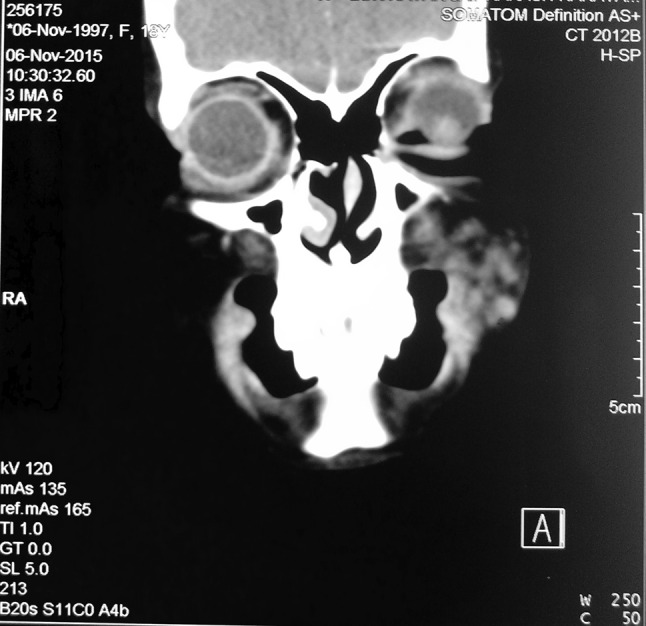

Contrast enhanced CT scan revealed an ill-defined, heterogeneously enhancing multilobulated lesion seen in subcutaneous plane of left cheek. There was no evidence of any bony erosion or intraoral extension as seen in Fig. 2 and Fig. 3.

Fig. 2.

Coronal section of contrast enhanced CT scan of the facial region showing heterogeneously enhancing, multilobulated lesion